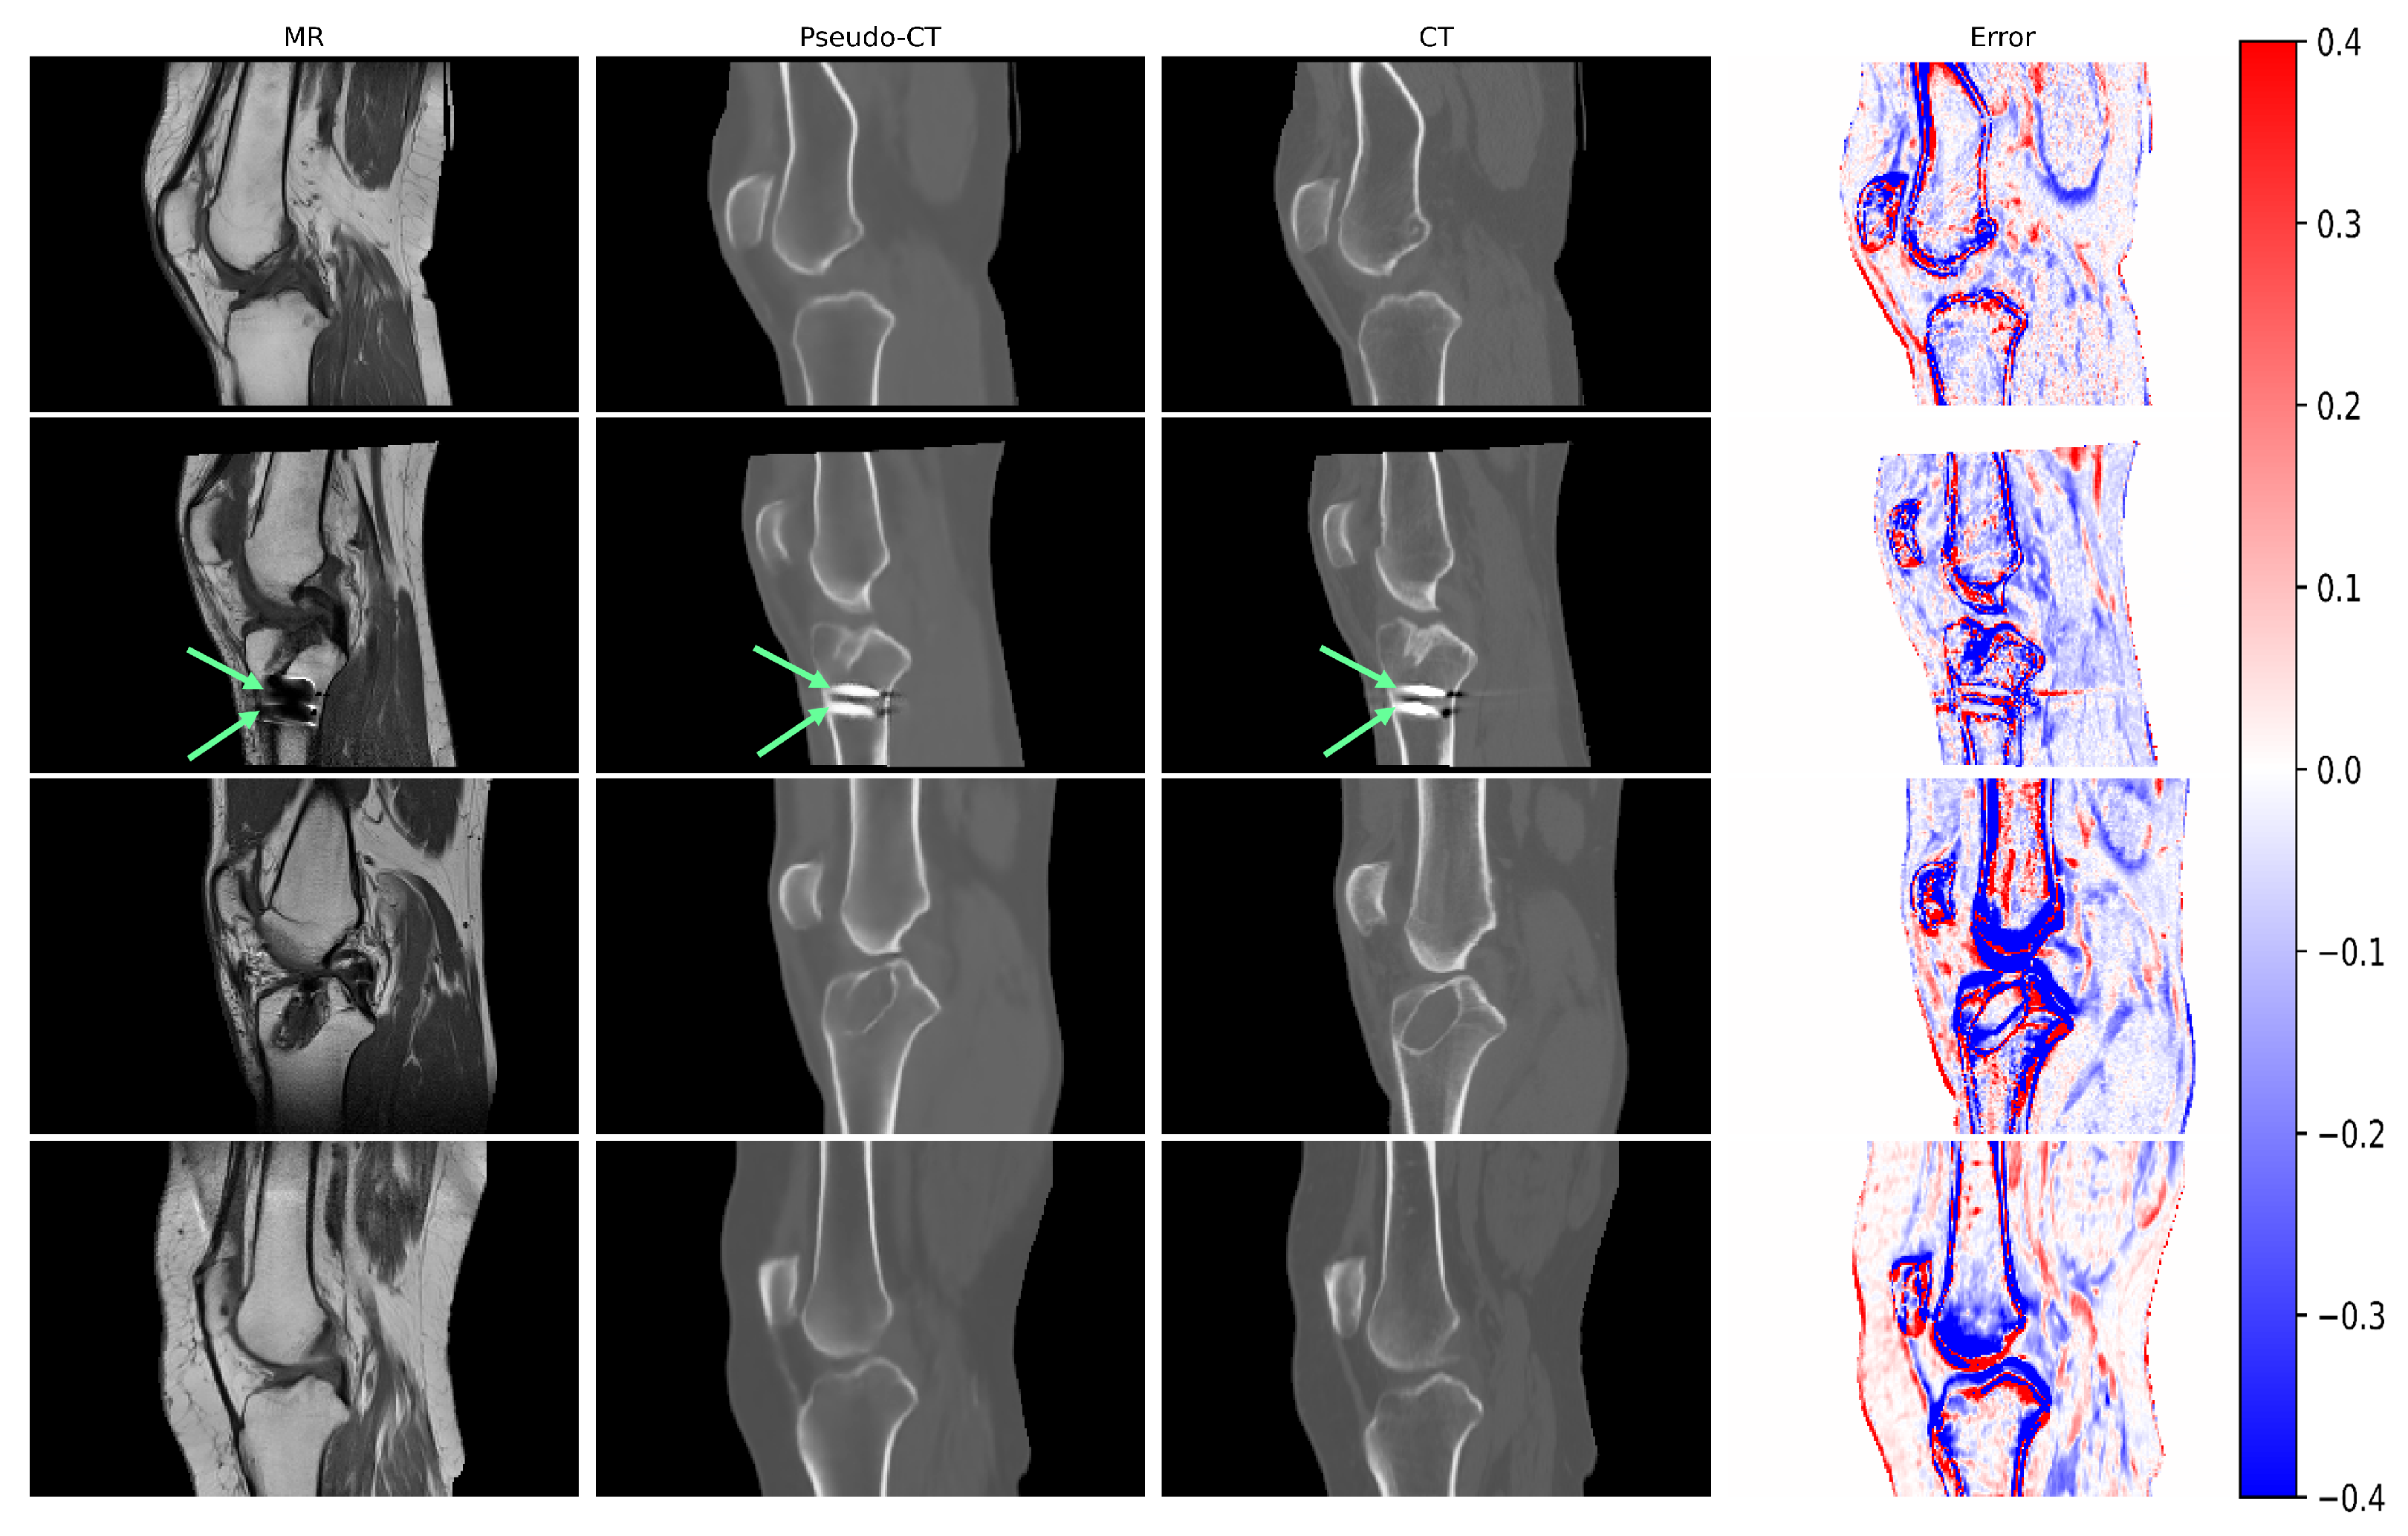

3.1. Qualitative Results